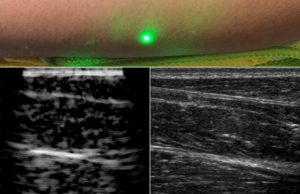

Researchers produce first laser ultrasound images of humans

For most people, getting an ultrasound is a relatively easy procedure: As a technician gently presses a probe against a patient's skin, sound waves...